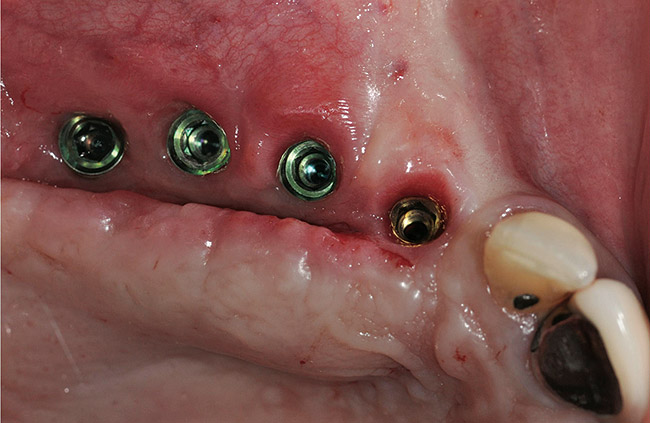

A 72-year-old man was referred for removal of failing maxillary right posterior implants (Figure 19). The treatment plan included removal of three implants with simultaneous bone augmentation and replacement implants for implant-supported fixed bridgework. Implant removal and bone grafting with rhPDGF (Gem 21®, Osteohealth, www.osteohealth.com) and allograft (MinerOss) and xenograft (BioOss®, Geistlick, www.geistlickonline.com) were used along with titanium mesh for space maintenance (Figure 20, Figure 21 and Figure 22). Six months later, mesh removal revealed type I bone allowing for placement of three implants (Figure 23 and Figure 24).

Figure 19  Failing implants in the right posterior maxilla.

Figure 19

Figure 20  Removal of the failing implants.

Figure 20

Figure 21  Bone grafting with rhPDGF, allograft, and xenograft.

Figure 21

Figure 22  Titanium mesh fixation.